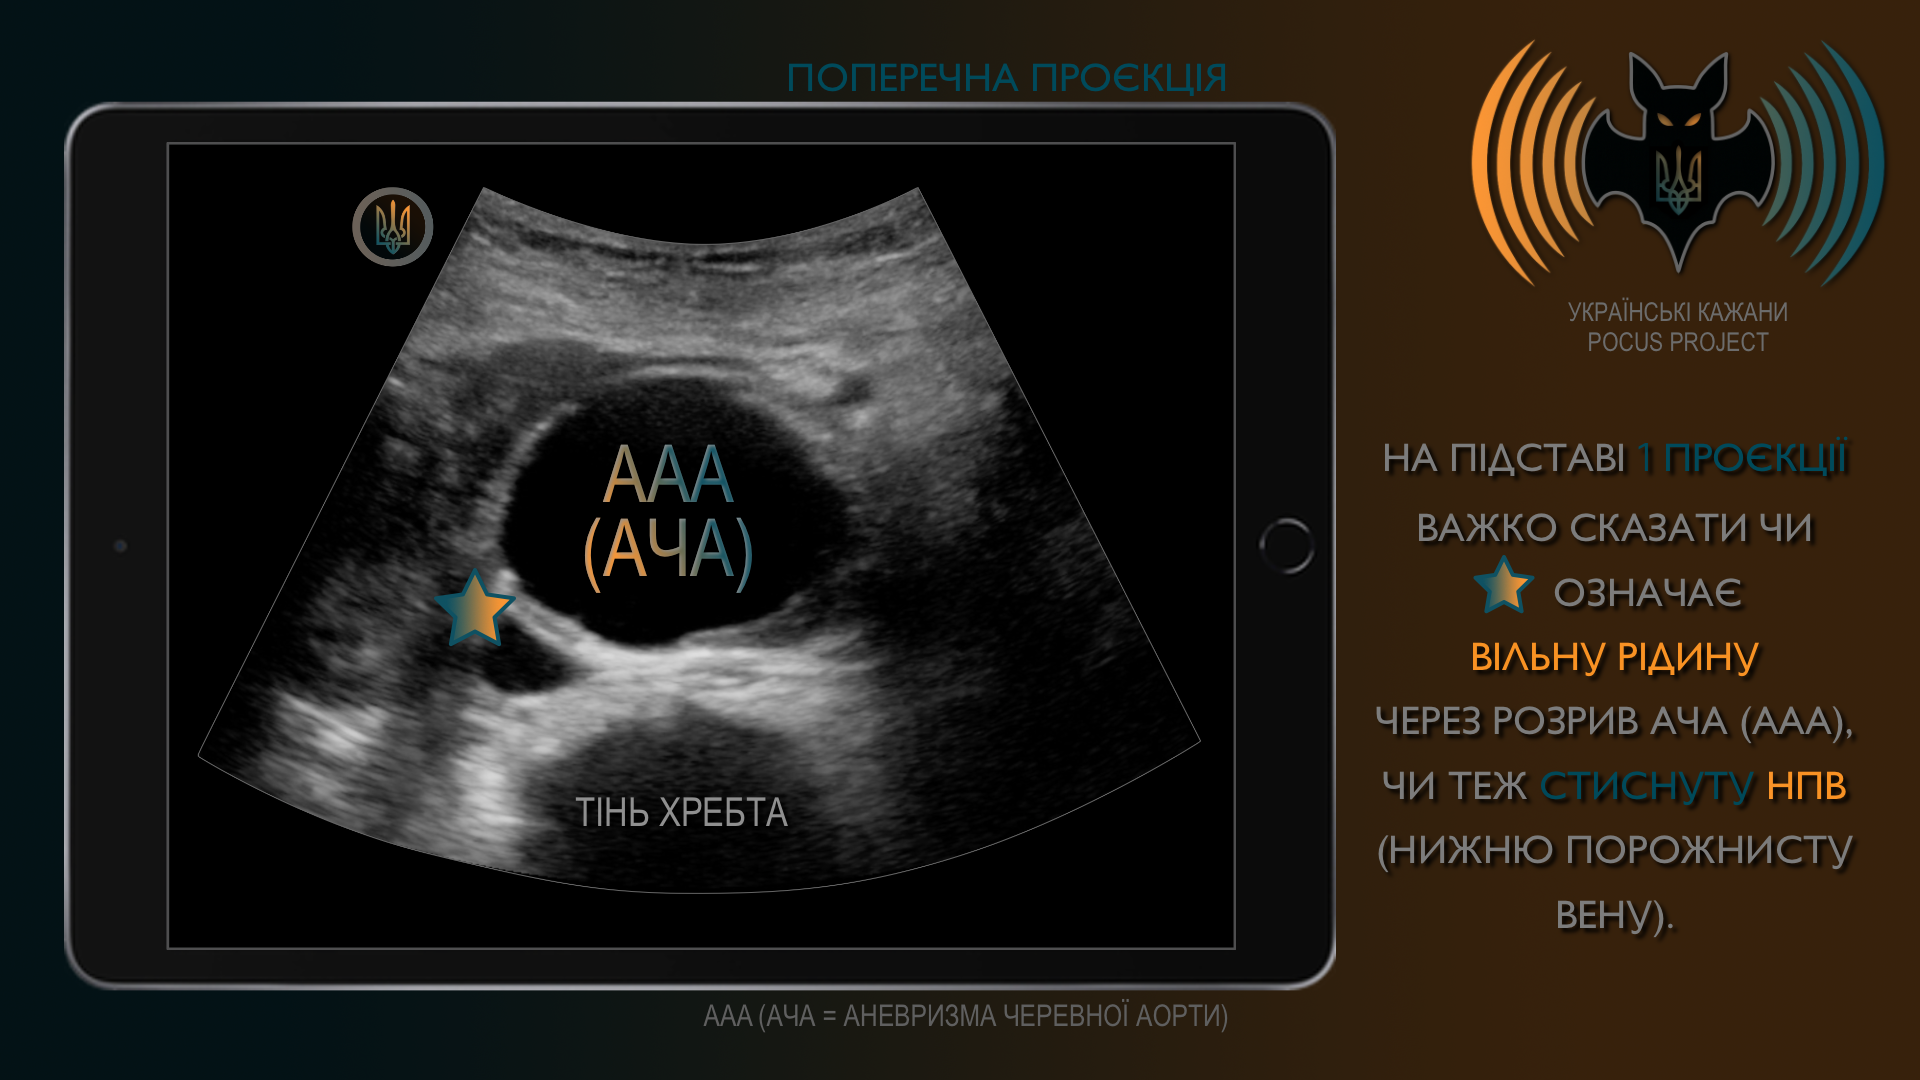

ПРИНЦИП №4: 1 проекція − не проекція! Як мінімум 2 площини. Читайте далі ➤

Те, що ми бачимо лише в одній проєкції, не завжди дає повну картину. Тому рекомендовано підтверджувати ультразвукові знахідки щонайменше у двох площинах. Оскільки ж ми відтворюємо тривимірну реальність у вигляді серії двовимірних зображень, необхідно просканувати датчиком усю клінічно релевантну зону.